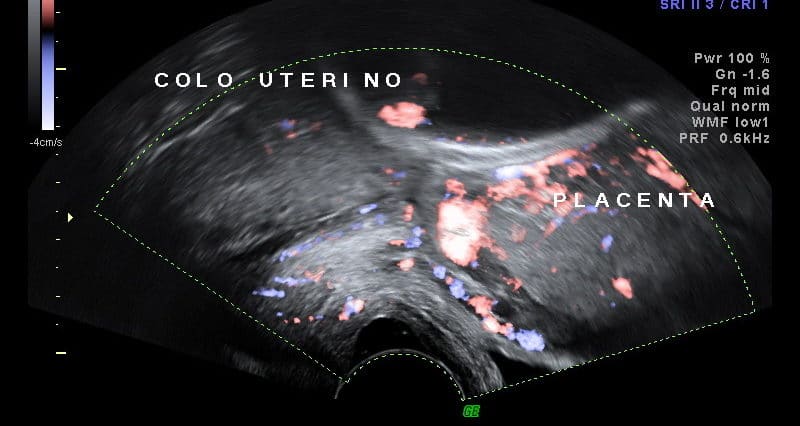

A placenta prévia é uma complicação obstétrica onde a placenta está inserida numa região próxima ou recobrindo o orifício cervical.